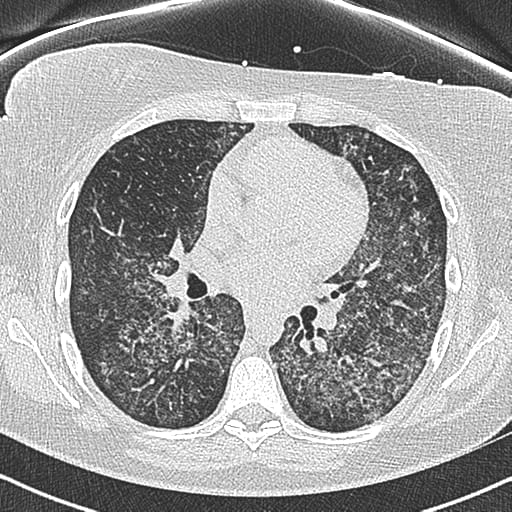

A pre-procedural HRCT confirmed our suspicion, revealing the characteristic diffuse ground-glass opacities bilaterally, signifying active alveolar filling.

Diffuse Alveolar Hemorrhage (DAH)

Pediatric DAH is a life-threatening syndrome characterized by the extravasation of red blood cells from the pulmonary microvasculature into the alveolar spaces. Unlike localized pulmonary hemorrhage, DAH is typically diffuse and leads to acute hypoxemic respiratory failure and profound anemia.

The classic triad of hemoptysis, anemia, and diffuse pulmonary infiltrates is a red flag, but often unreliable in our population. This is why a high index of suspicion, coupled with an interventional readiness, is mandatory.